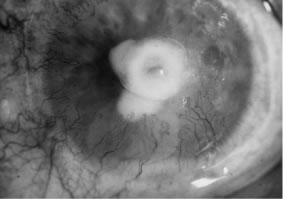

There is no distinguishing clinical sign by which to recognize the genus or species of the infectious filamentous fungus. F. solani is the most virulent organism and typically produces rapidly progressive infection characterized by epithelial and stromal ulceration, dense stromal necrosis, abundant cellular infiltrate, and edema in the adjacent stroma and hypopyon (Figs. 8 and 9). Delicate feathery components are transient. Individual hyphal fragments are rarely visualized. Infection by certain species of Aspergillus and Scedosporium (Figs. 10 and 11) resembles F. solani keratitis and progresses rapidly. Infection by less virulent organisms, such as Curvularia and Alternaria species, produces small, focal (less than 3-mm diameter) areas of nonnecrotizing stromal inflammation with delicate feathery borders (see Fig. 1 and Fig. 12). Macroscopic pigmentation may develop in keratitis caused by Alternaria, Curvularia, and other dematiaceous fungi (Fig. 13).4,11,14 The central component may progress to dense, opaque, gray-white suppuration in the deep stroma without enlargement in total area and may be accompanied by mild inflammation in the adjacent stroma. Iritis is minimal to moderate. Infection caused by other, relatively less virulent organisms resembles herpes simplex or noninfectious keratitis (Fig. 14).

Fig. 8. F. solani keratitis. Note the dense opaque central necrosis surrounded by fluffy, nonhomogeneous infiltrate.

Fig. 9. F. solani keratitis. Epithelial and stromal ulceration and necrotizing stromal keratitis.